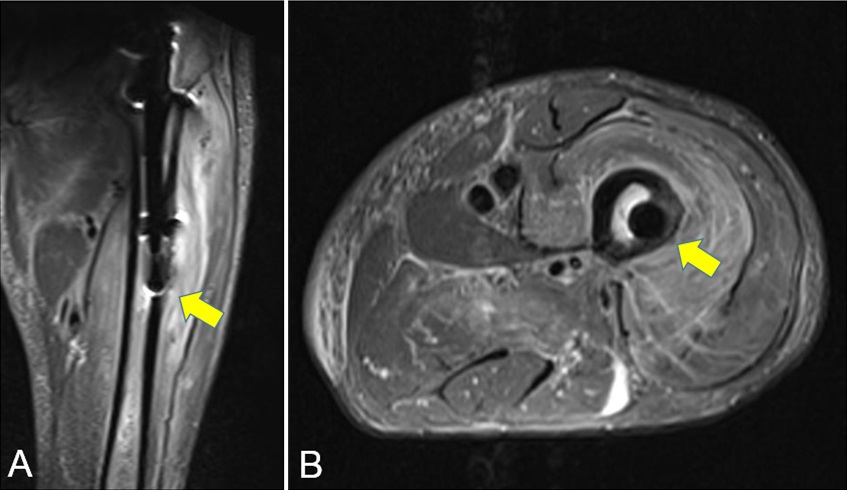

Penetración de la cortical anterolateral en fracturas de fémur proximal tratadas con clavos endomedulares cortos Reporte de dos casos. [Penetration of anterior-lateral cortex in proximal femur fractures treated with short intramedullary nails Report of two cases].

7. Ostrum RF, Levy MS. Penetration of the distal femoral anterior cortex during intramedullary nailing for subtrochanteric fractures: a report of three cases. J Orthop Trauma 2005;19:656-60.

9. Egol KA, Chang EY, Cvitkovic J, Kummer FJ, Koval KJ. Mismatch of current intramedullary nails with the anterior bow of the femur. J Orthop Trauma 2004;18:410-5.